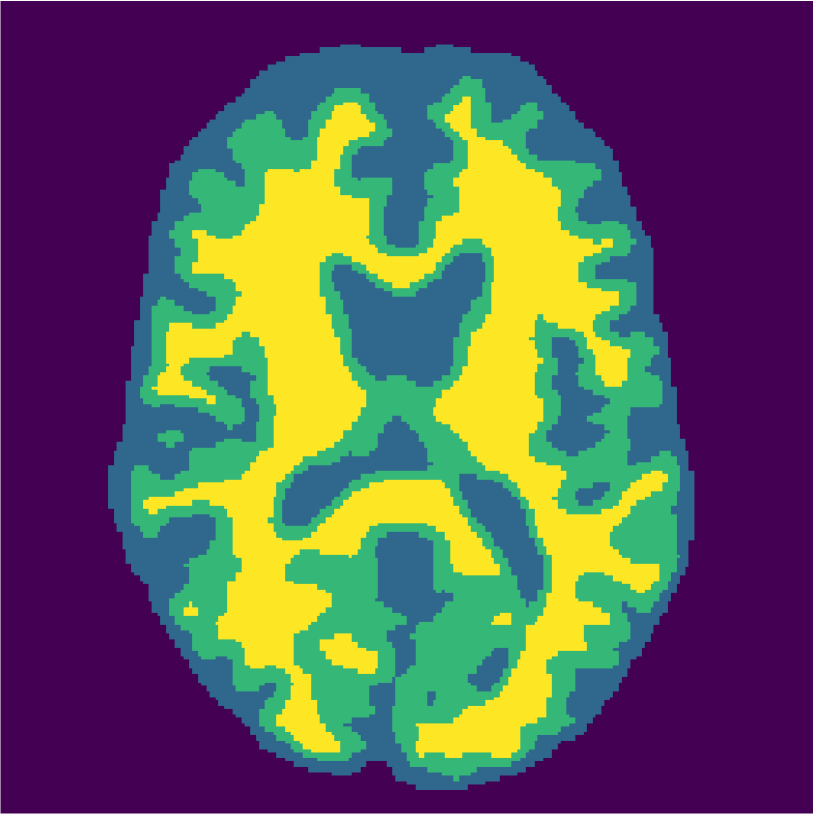

Appendix A describes the nuclear magnetic resonance (NMR) relaxation times for the tissues in the Brainweb anatomical models, for 1.5 and 3.0 Tesla field strengths. The tissues in the anatomical models are grouped into ”background” (BKG), ”cerebrospinal fluid” (CSF), ”gray matter” (GM), and ”white matter” (WM) to compose the ground truth segmentation labels for the simulated scans. The simulations result in images of 256 by 256 pixels, with a 1.0x1.0mm resolution. Figures 5(a) and 5(b) show examples of the Brainweb1.5T and Brainweb3.0T scan of the same subject. For all scans, we used a brain mask to strip the skull.

In order to test the proposed method on real data, we use the publicly available training data (5 subjects) from the MRBrainS challenge444http://mrbrains13.isi.uu.nl/Figure. The acquisition parameters used for simulating the Brainweb3.0T are based on the MRBrainS acquisition protocol (3.0T scanner, gradient-echo, B0 = 3.0T, = flip angle, TE = 4.5ms, and TR = 7.9ms). Figure 5(c) shows an example of an MRBrainS scan. Again, a brain mask is used to strip the skull.

Examples of the segmentation results on one of the target test images are shown in Figure 8 for experiment 2.1, Figure 9 for experiment 2.2, and Figure 10 for experiment 2.3. Examples are shown after using 1 target patch per tissue for training, and after using 100 target patches per tissue for training. The results show that only the mrai-net classifier is able to predict a segmentation that approaches the ground truth with only 1 target patch per tissue for training (error for experiment 2.1 = 0.269, experiment 2.2 = 0.403, experiment 2.3 = 0.320), while the source and target classifiers cannot (source error for experiment 2.1 = 0.667, experiment 2.2 = 0.653, experiment 2.3 = 0.435; target error for experiment 2.1: 0.591, experiment 2.2: 0.614, experiment 2.3 = 0.596). After using 100 patches the source and target classifiers can predict a gross segmentation of WM, GM and CSF (source error for experiment 2.1 = 0.213, experiment 2.2 = 0.384, experiment 2.3 = 0.363; target error for experiment 2.1: 0.205, experiment 2.2: 0.368, experiment 2.3 = 0.368), but the mrai-net classifier prediction shows more details and a lower tissue classification error (error for experiment 2.1 = 0.111, experiment 2.2 = 0.276, experiment 2.3 = 0.284).